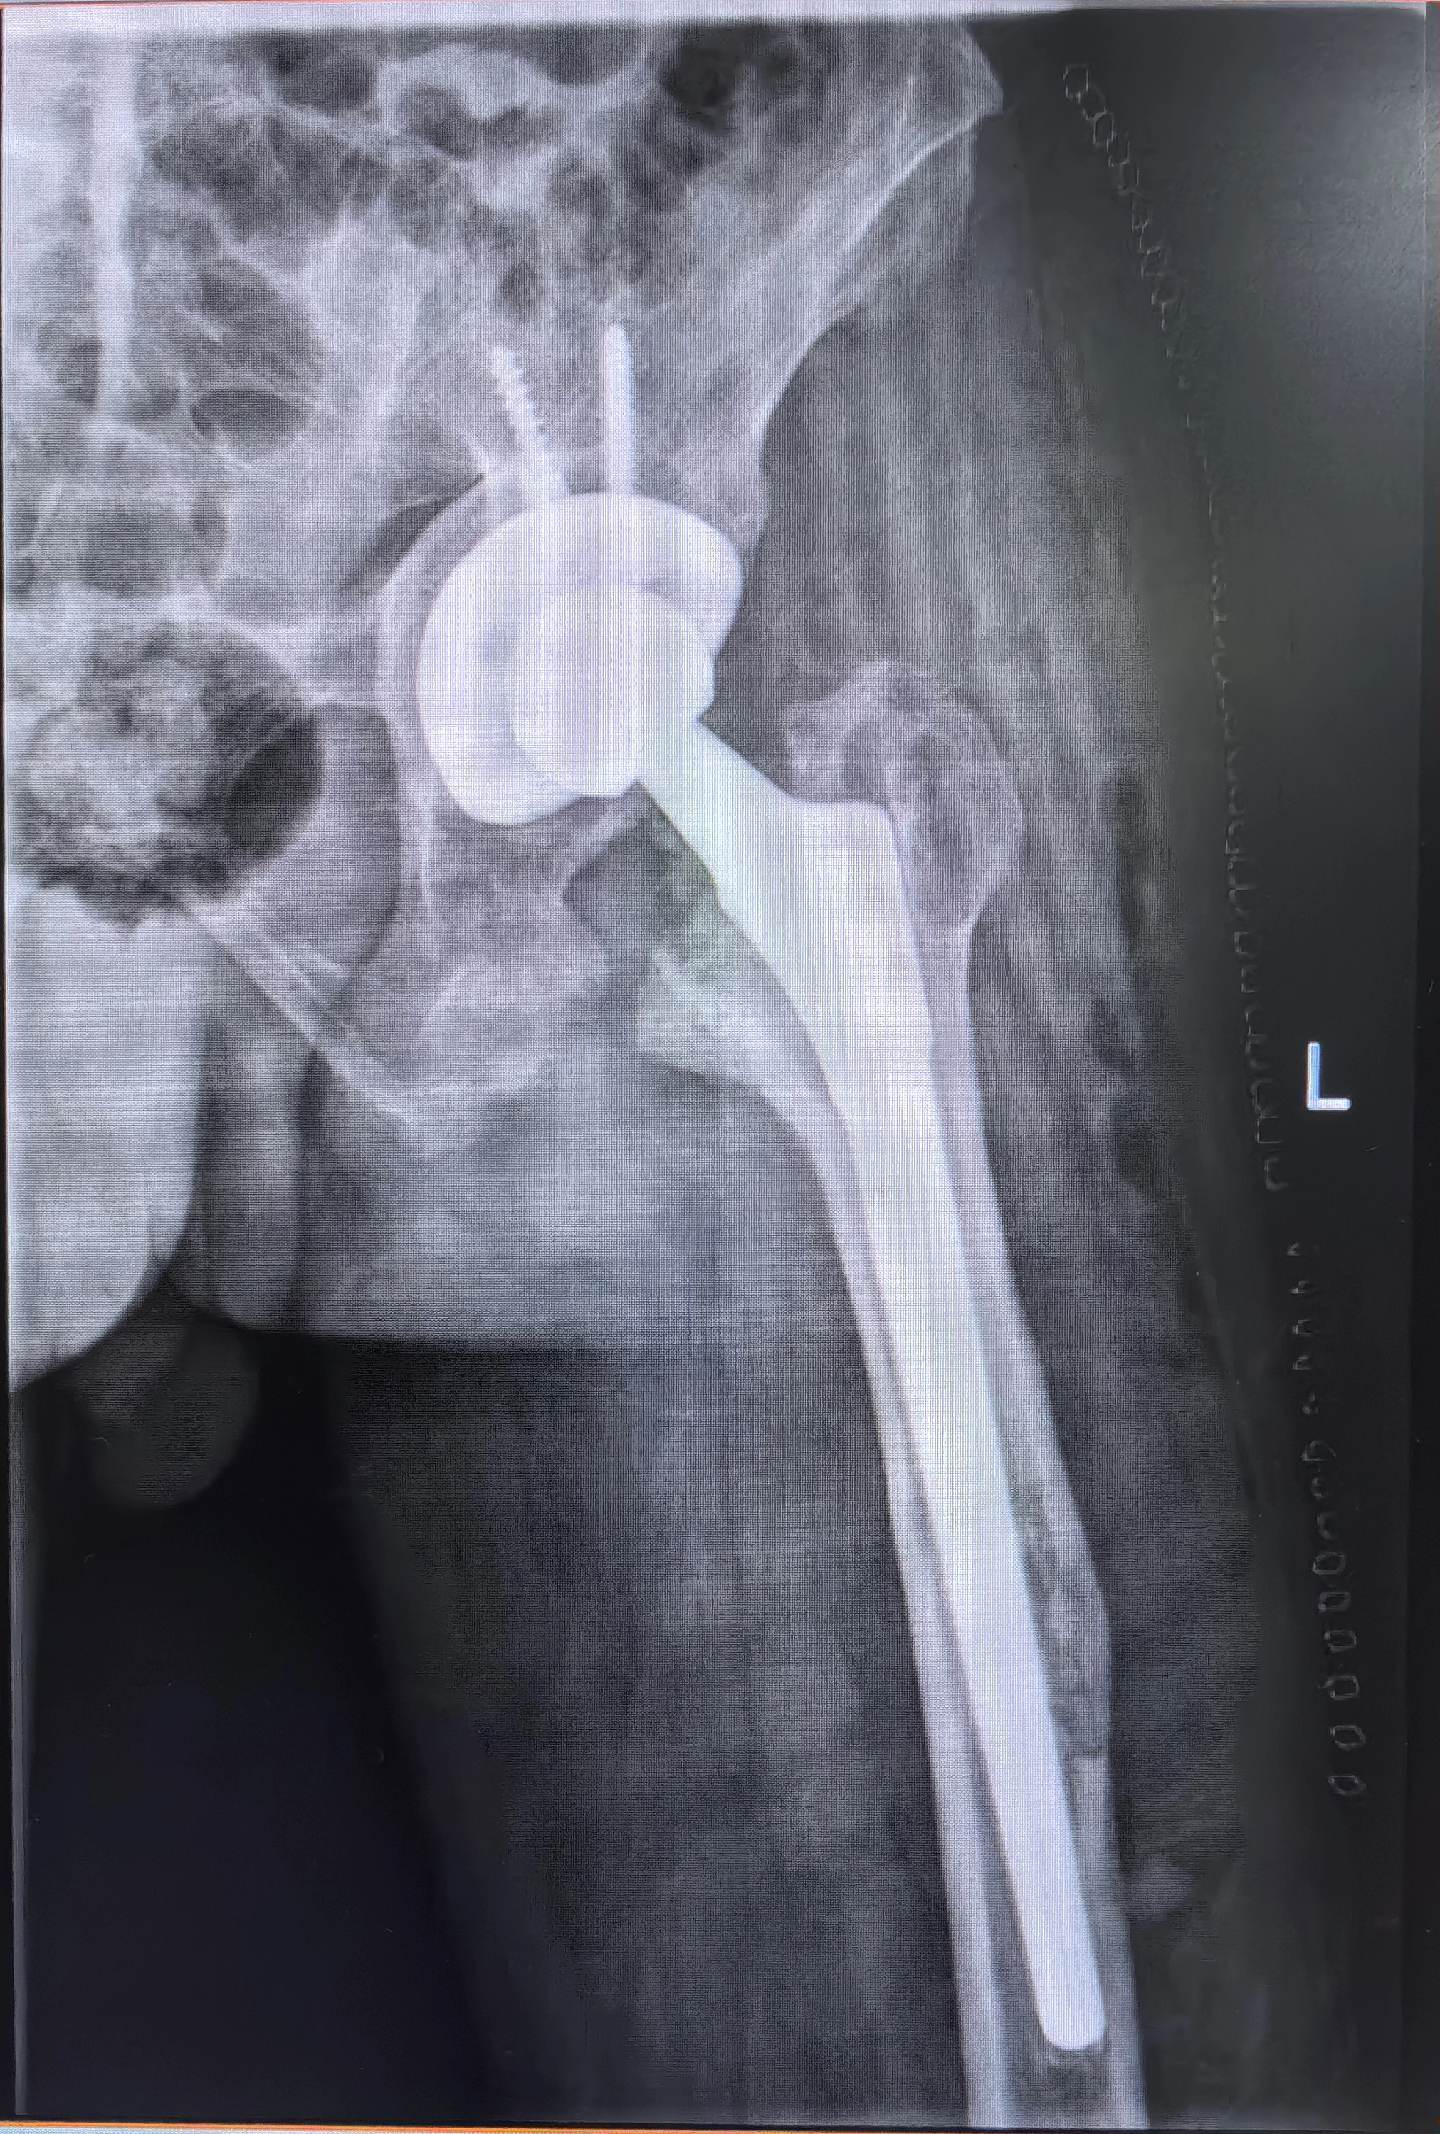

髋关节翻修。强脊炎THA后假体松动,术前短3cm,术后等长。难点:松动的股骨柄远端硬化如何突破?实际操作起来真的不容易。此例虽有插曲,好在医院大平台器械完备,结局满意,术后2天正常下床走路🌹